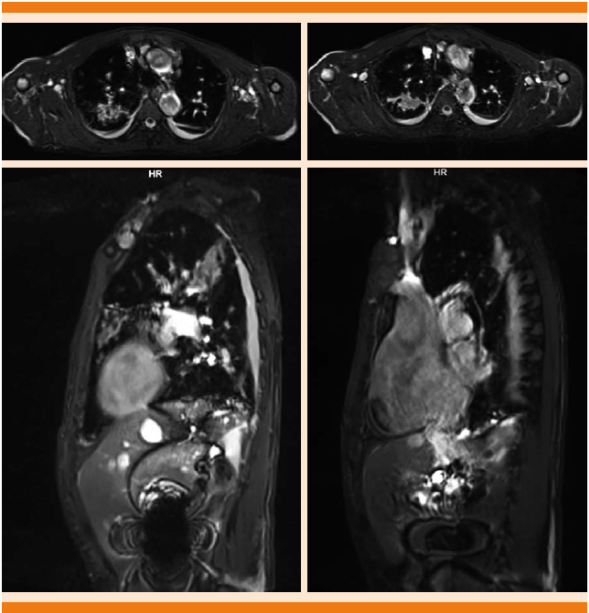

Malformación arteriovenosa pulmonar en la región apical derecha evidenciada en resonancia magnética nuclear de 69.4 x 26.1 x 51.4 mm (Figuras 2 y 3).

Figura 2 Imagen potenciada en T2, corte axial y sagital, en donde se observa una lesión irregular, heterogénea, predominantemente hiperintensa, en la región apical derecha, derrame pleural bilateral, existe, además, crecimiento global de las cavidades cardiacas, valorable en los cortes sagitales.

Figura 3 Imagen potenciada en T2, FAT SAT, corte coronal y axial, en donde se identifican en el hemitórax derecho múltiples lesiones irregulares, hiperintensas en relación con el resto del parénquima pulmonar, que demostraron corresponder a malformaciones arteriovenosas.